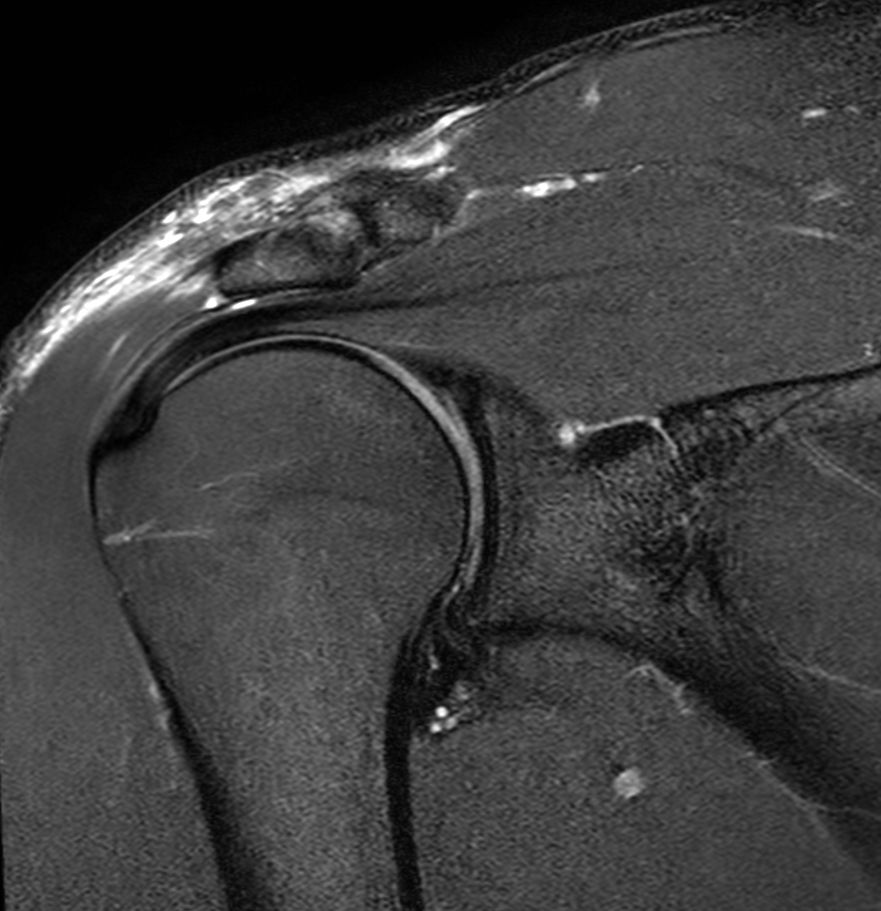

Coronal T2w SPAIR